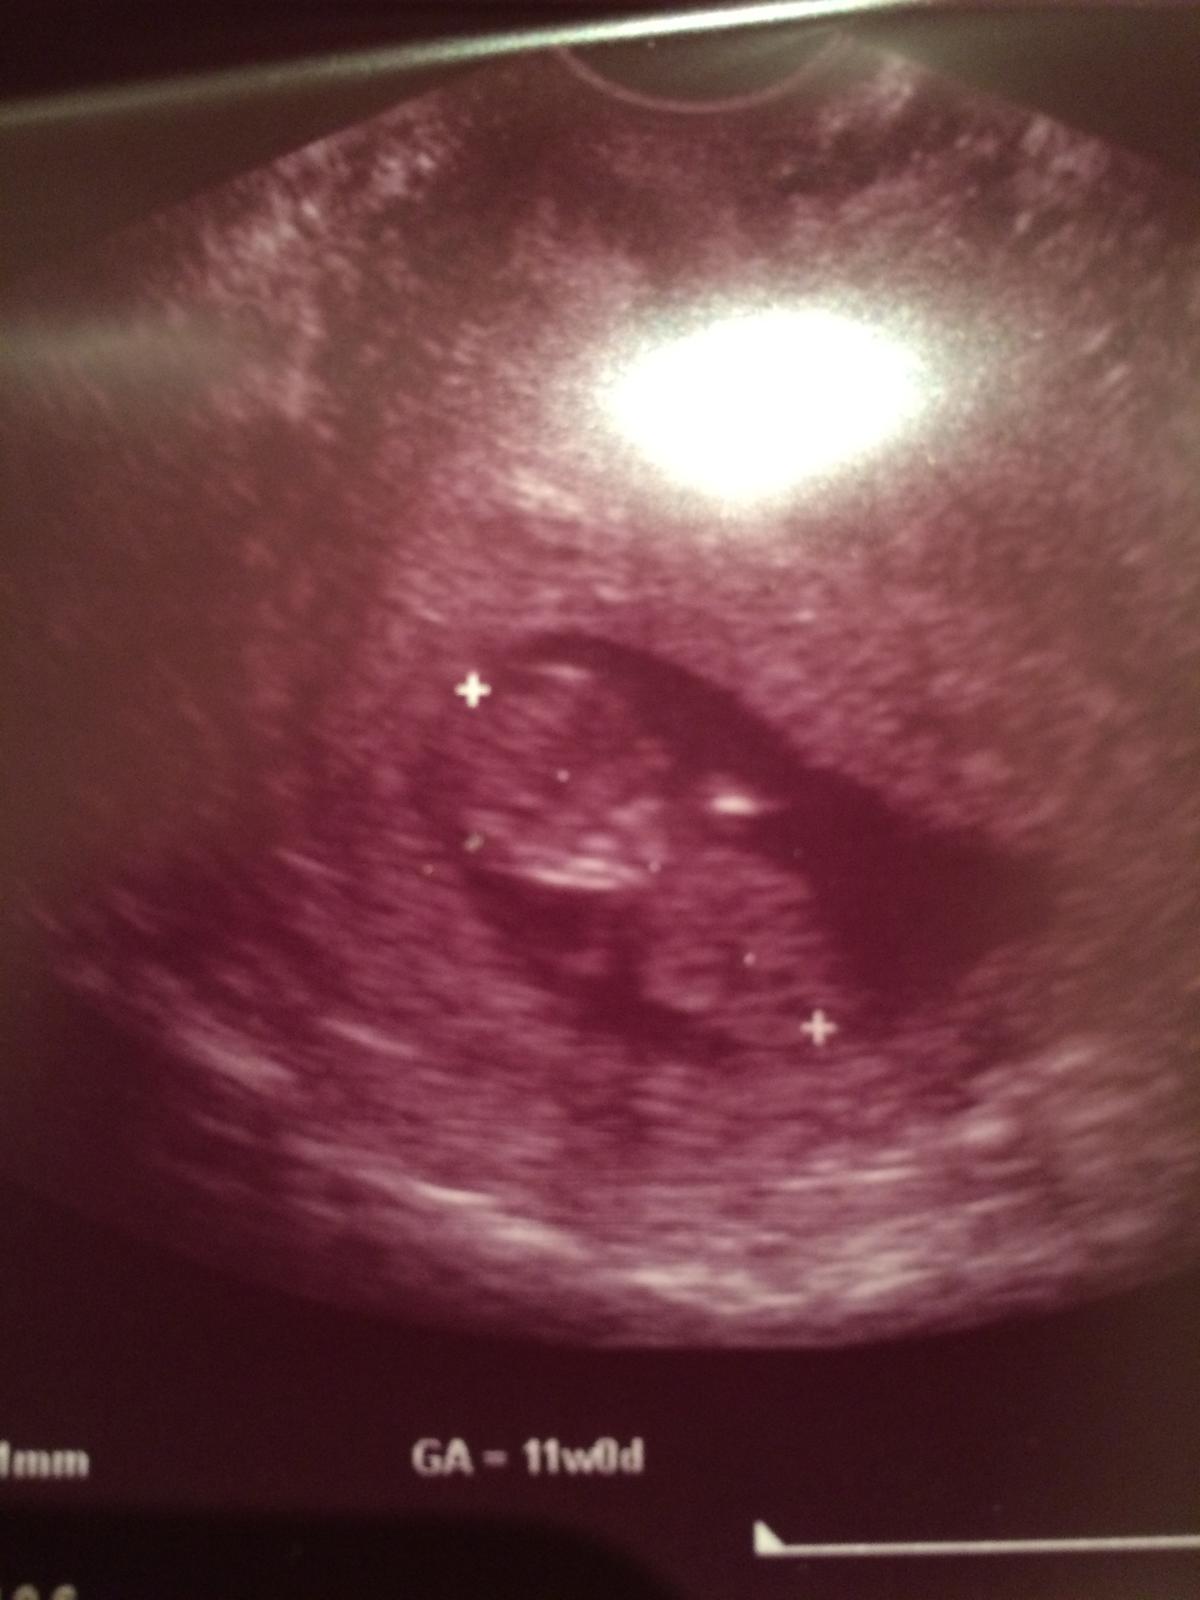

@sara34valentina @wewitta @mimikas @agathachristie @sara22 @melisssssa @evi789 ajojte dievcence moje tak ja uz mam to NT meranie za sebou, doktorka poriadne z kazdeho uhla popozerala drobceka, vyzera to tak ze je zatial vsetko v najlepsom poriadku, mame uz skoro 5cm a zistili sme ze drobec bude asi maly hamblosko po ocinkovi lebo ani za nic doktorke neukazal/a co medzi nozkami skryva 🙂 Dalsiu poradnu mame az 12.1. takze teraz mame pauzu od doktorov 🙂

@mimikas jeeej drobculiatko malinkeeee, presne tyzden je medzi nimi 😵 Mne dnes vyslo z utz ze som 12+0 🙂